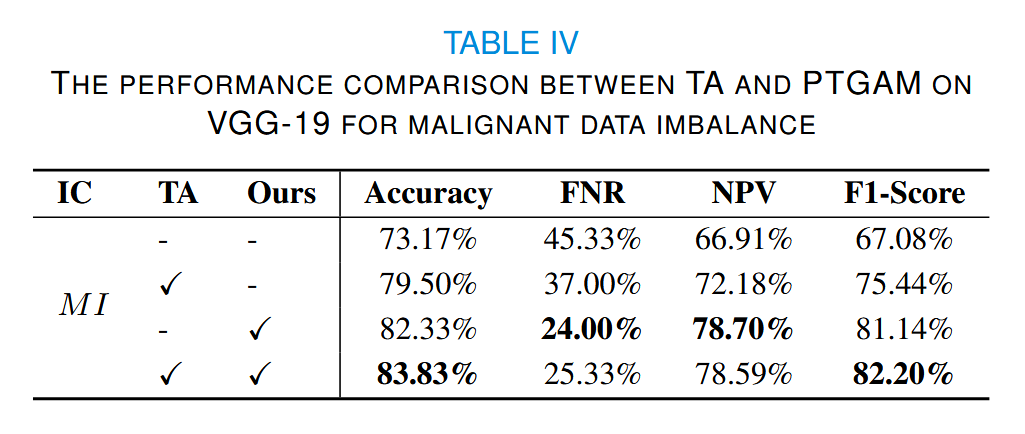

此外,我们还对恶性数据进行了数据增强实验,使其数据量与良性数据的数据增强设置大致相同。可以看出(表IV),我们的方法对每个类别具有相同的增强效果。

表IV中的 NPV 表示阴性预测值,即 TN/(TN + FN) 。

在良性数据稀缺的情况下,模型倾向于陷入偏向恶性类别的局部最优解。因此,我们选择假阳性率(FPR)和精确率来衡量不同增强方法的效果。可以看出,我们的方法能够显著减少假阳性。

当恶性数据稀缺时,我们选择假阴性率(FNR)和NPV。结果表明,当我们的方法与 TA 结合时,可以获得最高的准确率。然而,在FPR和FNR方面,我们的方法最大限度地减少了数据偏差的不良影响。